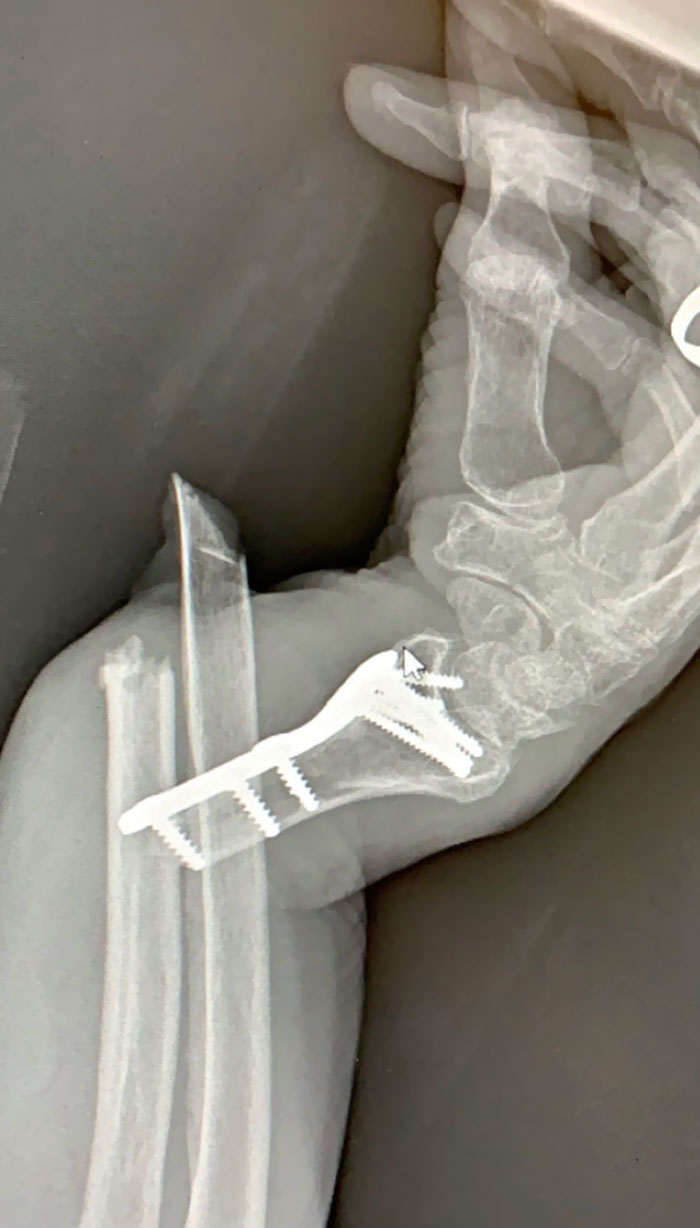

X-Ray Of My Metal Arm

X-Ray Of My Arm After Amputation, Thanks To Driver Who Fell Asleep At The Wheel